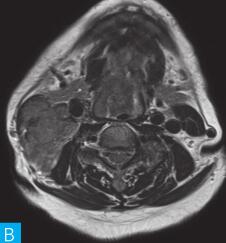

喉咽部MRI检查:病人采取仰卧位,横断位扫描为主,包括T1WI、T2WI及T2WI脂肪抑制序列,扫描范围自鼻咽部至喉咽以下,扫描层厚为3.5mm、层间隔0.35mm,矩阵512×512;辅以冠状位T2WI,矢状位T2WI序列及脂肪抑制序列,平扫后行横断位、冠状位及矢状位的增强扫描,造影剂量0.2ml/kg。见图1。

图1 咽喉部MRI:A.喉咽部MR横断面平扫T1WI;B.喉咽部MR横断面T2WI;C.喉咽部MR横断面T2压脂;D.喉咽部MR横断面增强T1WI;E.喉咽部MR冠状面T2WI;F.咽喉部MR冠状面增强T1WI

MRI平扫可见右侧扁桃体较大的软组织肿块,T1WI呈稍低信号,T2WI呈稍高信号,信号较均匀,T2WI压脂序列上呈高信号,病变与右侧咽扁桃体及舌根部分界不清,左侧咽扁桃体肿大,口咽腔明显变形狭窄,病灶延伸至喉前庭;双侧锁骨上窝及颈血管鞘周围间隙内可见多发大小不等的肿大淋巴结,大部分肿大淋巴结信号较均匀,呈稍高信号,边界清楚,右侧颈部间隙内个别肿大淋巴结内见少量斑片状液化坏死区;增强扫描后下咽部病变及双侧颈部间隙内的肿大淋巴结均呈明显的较均匀强化,提示该两处占位病变的血供较为丰富,且可能为同源性病变,因此采取“一元论”诊断思维进行分析更为合理。

(1)发现病变与认证:扁桃体及颈部病变较为容易发现,主要是分析两方面:一是仔细观察咽部有无原发病变,原发病变的形态及信号;二是评价淋巴结的分布,淋巴结的信号及生长特点。本病例基本征象为扁桃体病变信号均匀,无坏死,颈部淋巴结分布广泛,信号均匀。

(2)定位诊断:对于本病例来说,发现两处病变,包括咽部和颈部。咽部的病变位于扁桃体,延伸至喉咽腔,口咽腔和梨状窝受压变窄。颈部的病变为多发淋巴结增大,淋巴结广泛分布于Ⅱ~Ⅴ区。

本病例的特点为右侧扁桃体肿块,病变边界较清楚,表面光滑,信号均匀。双侧颈部间隙内多发肿大淋巴结,淋巴结围绕颈动脉鞘,部分病变融合倾向,广泛分布于Ⅱ~Ⅴ区,增强后病变较明显强化。

该病例首先对病变进行定位,包括咽部的和颈部的。咽部的病变:病变位于扁桃体,延伸至喉咽腔,口咽腔和梨状窝受压变窄(引起异物感和吞咽困难的原因)。颈部的病变:多发淋巴结增大,淋巴结广泛分布于Ⅱ~Ⅴ区。扁桃体病变的信号特征:扁桃体病变表面光滑,提示黏膜完整,病变来源于黏膜下,病变信号均匀,无坏死,进一步支持病变来源于黏膜下。颈部淋巴结病变的特征:淋巴结分布广泛,信号均匀(可以初步排除结核和转移,后两者容易坏死),围绕颈动脉鞘,但是不侵犯颈动脉鞘(转移容易侵犯颈动脉鞘),部分淋巴结融合倾向(结核淋巴结增大,无融合倾向,而且容易坏死),病变中度强化,进一步支持颈部淋巴瘤的诊断。诊断原则:首先仔细观察咽部有无原发病变,原发病变的形态及信号,尤其黏膜是否完整。其次评价淋巴结的分布,淋巴结的信号及生长特点。